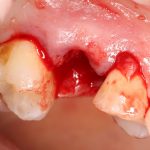

В общем, так и получилось. Уж не помню, почему я наобещал пациентке, что мы поставим ей имплантаты одновременно с остеопластикой. Но я наобещал. И, когда увидел клиническую картину в полости рта:

у меня появились серьезные сомнения, смогу ли я выполнить своё обещание. Вот только не спрашивай меня «Вот чо, сложно было по КЛКТ посмотреть?». Я же не спрашиваю тебя, где ты был в 2013 году, и сделал ли ты домашку. Но, в целом, план операции у нас не поменялся. Как и было оговорено, мы проведем остеопластику с одновременной имплантацией в боковом участке нижней челюсти справа.

Кстати, обрати внимание на ширину альвеолярного гребня (левая картинка). Она чуть меньше 3 мм. Это объясняет, почему я засомневался в возможности установки имплантатов одновременно с остеопластикой. Понятно и без КЛКТ.